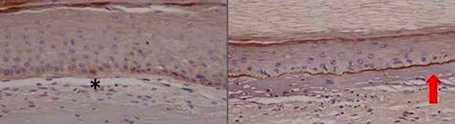

Improve the efficiency and accuracy of genomics edition for the treatment of epidermolysis bullosa

Improve the efficiency and accuracy of genomics edition for the treatment of epidermolysis bullosa. Epidermolysis bullosa or butterfly skin disease is characterized by extreme skin...